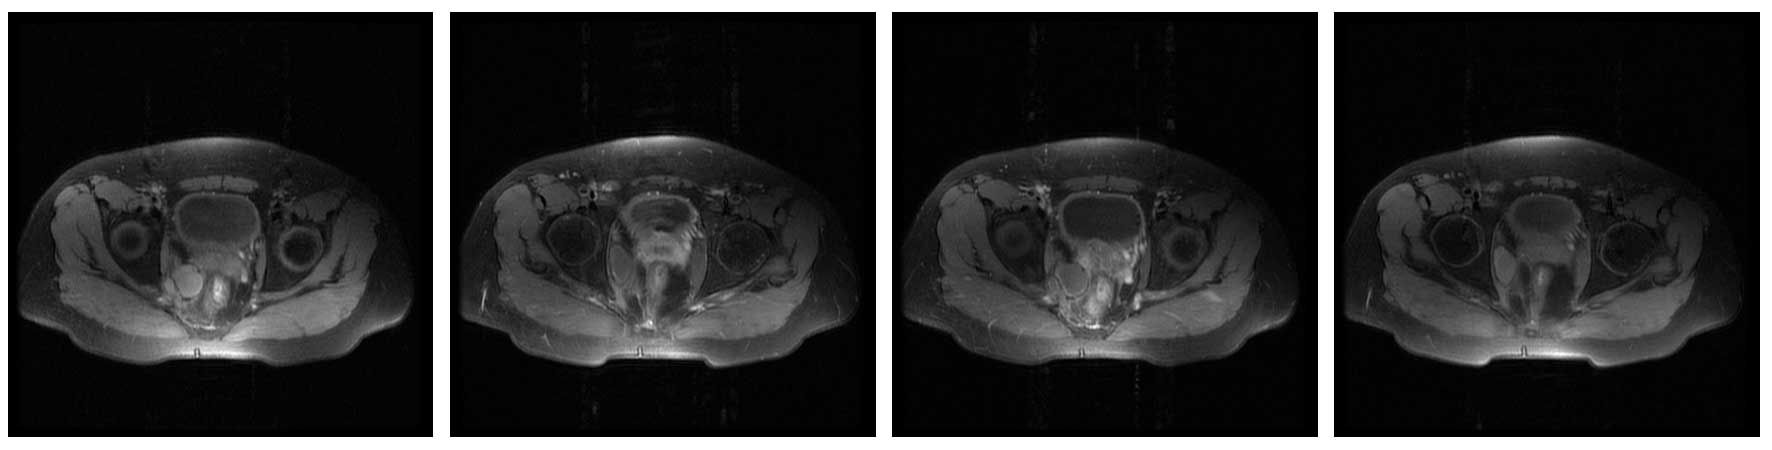

Ameliyat Öncesi: MR’da sağ hemipelvis yerleşimli düzensiz sınırlı heterojen tümör dokusu görülmekte.